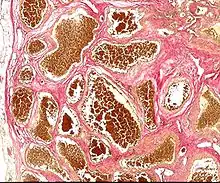

Histology of a cavernous hemangioma

Cerebral cavernous malformation (CCM) is a cavernous hemangioma that arises in the central nervous system. It can be considered to be a variant of hemangioma, and is characterized by grossly large dilated blood vessels and large vascular channels, less well circumscribed, and more involved with deep structures, with a single layer of endothelium and an absence of neuronal tissue within the lesions. These thinly walled vessels resemble sinusoidal cavities filled with stagnant blood. Blood vessels in patients with cerebral cavernous malformations (CCM) can range from a few millimeters to several centimeters in diameter. Most lesions occur in the brain, but any organ may be involved.[1]